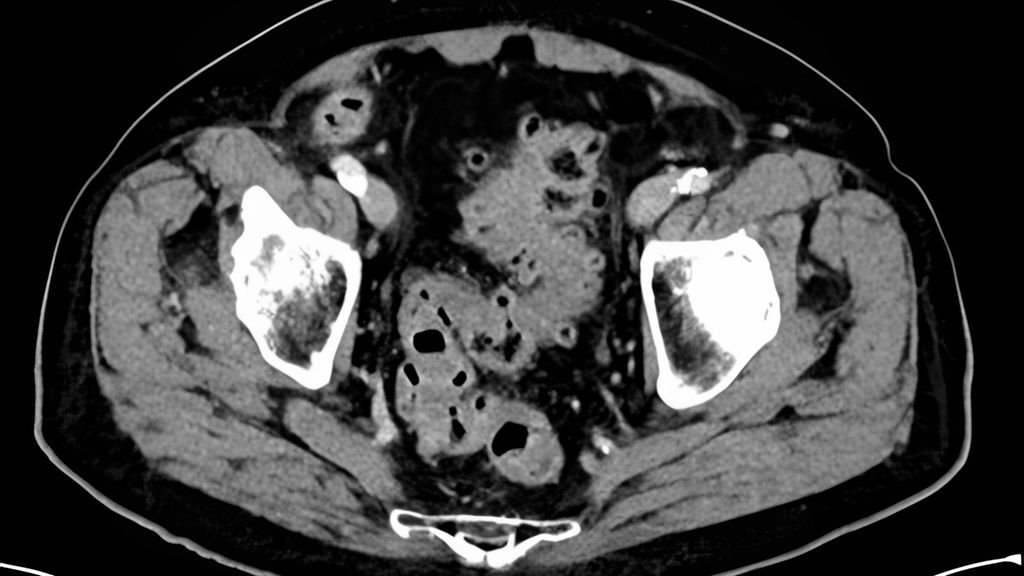

Klinisch imponiert hier meist eine milde Symptomatik mit dezent erhöhten Entzündungswerten, ohne Fieber, Sepsiszeichen oder Peritonitis. In der Bildgebung zeigt sich eine Entzündung der Divertikel, ggf. mit phlegmonöser Umgebungsreaktion (Abb. 1).

Abb. 1: CT einer Divertikulitis CDD 1b mit phlegmonöser Umgebungsreaktion